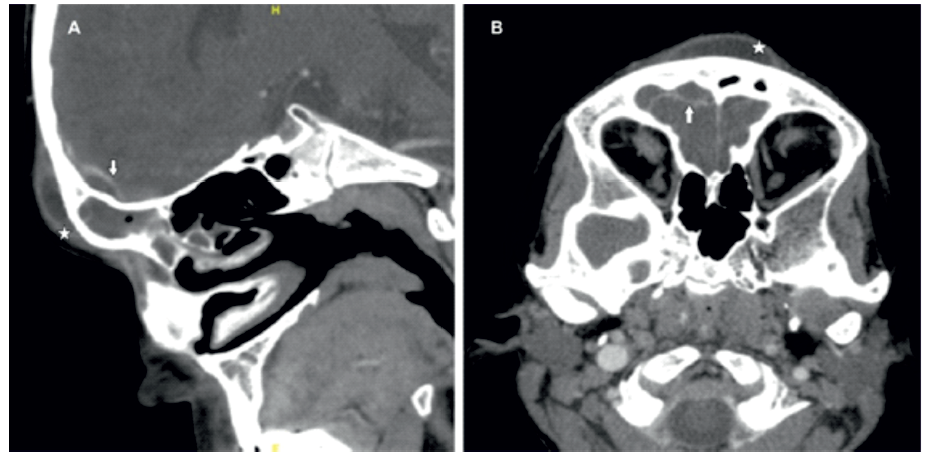

CT-scan presented occupation of the frontal sinuses and the anterior ethmoidal cells, right preseptal cellulitis and a frontal subperiosteal abscess (8x34x29mm) spreading intracranially through a frontal epidural empyema (8x38x23mm) (Fig.2).

Figure 2: Computed tomography (CT). Axial (A) and sagittal (B) post contrast computed tomography demonstrating a frontal subperiosteal abscess (*) and a frontal epidural empyema (arrow).